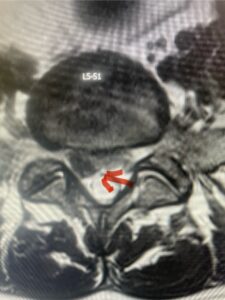

Figures 1a: Sagittal and axial T2-weighted lumbar MRIs demonstrating a grade 1 L2-3 spondylolisthesis (red arrow) with severe stenosis secondary to right L2-3 facet hypertrophy (red arrow).

In this next case, this patient is a 47 year-old female who presents with intractable low back pain with severe pain, numbness, and weakness in the right lower extremity that had gotten progressively worse over a year. The patient had failed conservative management including physical therapy and epidurals. She was noted to have ⅘ weakness of plantar flexion. MRI demonstrated a large right L5-S1 disc herniation with severe compression of the descending right S1 nerve root (Fig 3). It was decided to perform a right L5-S1 hemilaminectomy for removal of the disc fragment and decompress the S1 nerve root. When you expose the disc, one must be certain to release any anterior adhesions to the nerve root in order to prevent a dural tear during retraction of the nerve root. It is also important to make sure during exposure and you finally encounter the dura after removing the ligamentum and fat, to make sure you are looking at the nerve root and not the main trunk of the thecal sac because if you don’t you can avulse or damage the nerve root if you retract the wrong structure.

Fig. 3a: Sagittal and axial T2-weighted lumbar MRI images demonstrating large right L5-S1 disc herniation (red arrows)

We found a massive subligamentous herniation which had to be revealed by having your partner retract the freed nerve root with a nerve root retractor and putting slight downward pressure on the more medial and anterior disc space. There is nothing more satisfying when the jelly (disc fragment) of the annulus (donut) comes squirting out and you remove a large chunk of disc material that clearly was stretching the ligament membrane and compressing the nerve root. This does cause back pain in addition to radiculopathy not only by the component of mechanical compression but also the stretching of the nerves within the ligament. We performed this surgery and noted that the nerve root was a very angry red color or hyperemic and we removed a large subligamentous fragment. The patient had improvement of her preoperative radicular symptoms.